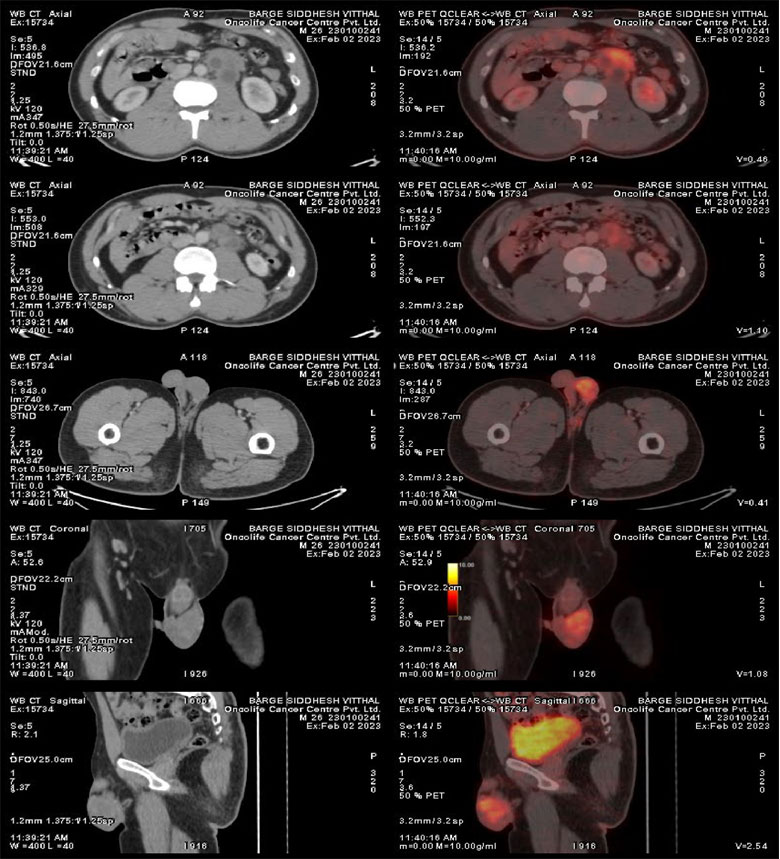

PET Scan 2/2/2023 S/O

H/o Left testicular mass, for evaluation.

1. Hypermetabolic mass lesion involving left testis – likely malignant etiology, for biopsy correlation.

2. Hypermetabolic paraaortic nodal mass – likely metastatic.

3. No significant metabolically active disease elsewhere in the whole-body survey.